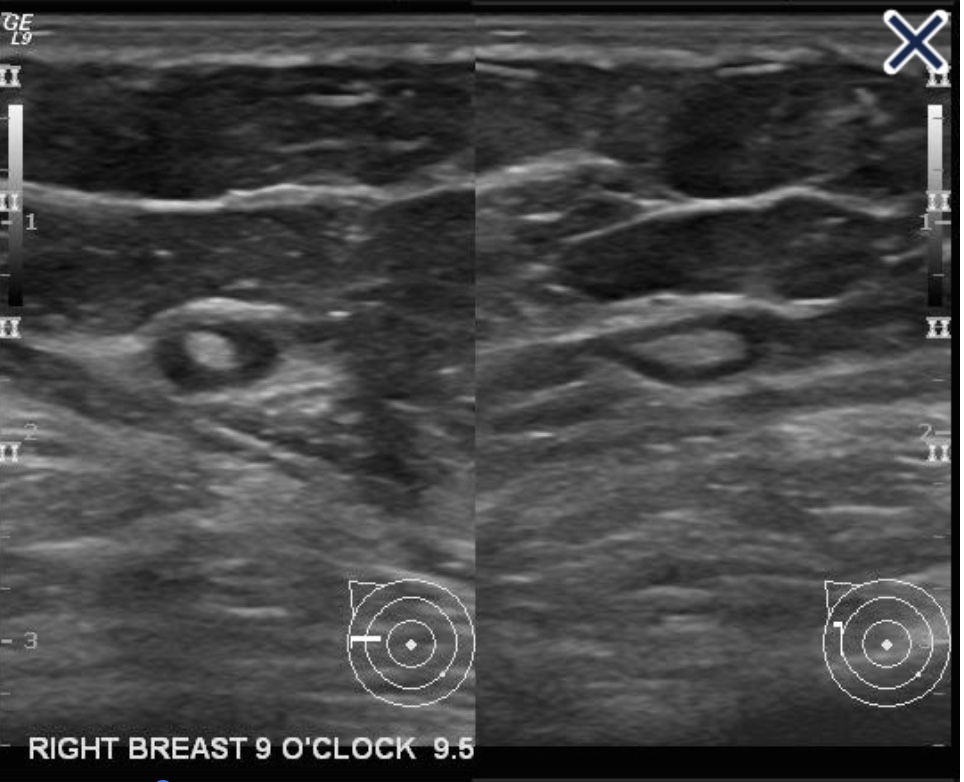

• The sonographic appearance of a normal lymph node:

• Is elliptical with a thin, hypoechoic cortex and an isoechoic to hyperechoic fatty hilum (Image).

Normal lymph node.